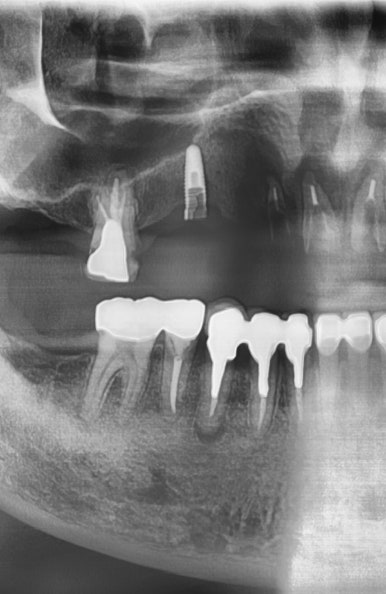

2."임플란트 뿌리부분이 쓰다보니 찢어져서 머리부분도 빠져버렸어요."

전 후 사진

흔들리는 옆 치아와 흔들리는 임플란트를 제거하고 임플란트2개와 임플란트 브릿지로 마무리

흔들리는 옆 치아1개와 흔들리는 임플란트2개를 제거하고

3개의 자리를 임플란트2개와 가짜머리1개가 있는 임플란트 브릿지로

3개의 자리를 마무리하였습니다.

1.흔들리던 임플란트 2. 임플란트 제거 후 3.임플란트 재수술 후